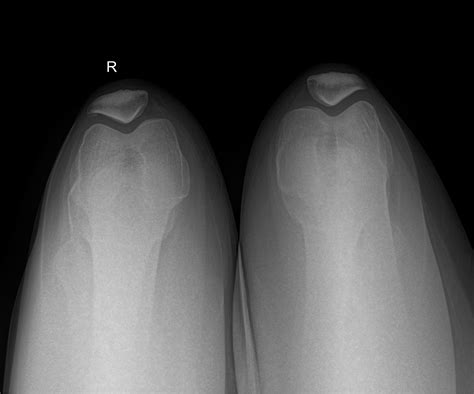

During the typical development of a human skeleton, the patella begins as multiple centers of ossification (bone formation). Usually, these centers fuse together during early adolescence to form one solid, singular bone. In individuals with a Bi Part Patella, this fusion process fails to occur completely, leaving a small accessory bone—most commonly located at the upper outer corner of the kneecap—separated from the main body of the patella.

⚠️ Note: It is critical to differentiate between a symptomatic bipartite patella and a recent patellar fracture. Unlike a fracture caused by sudden trauma, a bipartite patella typically features smooth, rounded edges on the separated bone fragments, which can be clearly visualized on X-rays.

Diagnosis usually begins with a thorough physical examination, during which a healthcare professional will press on the kneecap to locate the exact point of tenderness. To confirm the diagnosis and rule out other potential causes of knee pain, imaging studies are essential:

X-Ray The primary tool to visualize the separation in the bone.